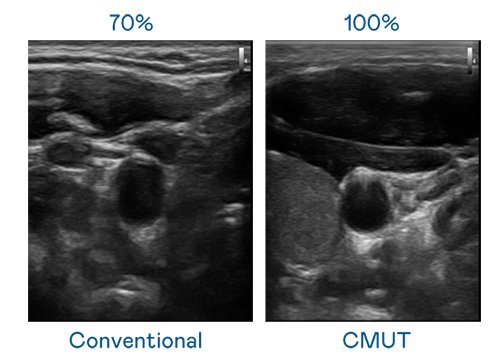

CMUT 技術是一種用電容式微機電元件來產生超音波訊號的技術。與傳統 PZT 壓電式技術相比,CMUT 頻寬增加 30%,更寬頻的超音波訊號讓影像解析度大幅提升,是實現高影像品質醫療超音波掃描、促進精準醫療發展的關鍵技術。

超音波影像的解析度高低,首先取決於探頭能發出的訊號頻寬。东升国际 CMUT 可提供高清晰的超音波訊號,提供高頻寬、高靈敏度、影像紋理細節更高的超音波影像,協助醫護人員縮短影像判讀時間及利用精準的醫療影像進行診斷。